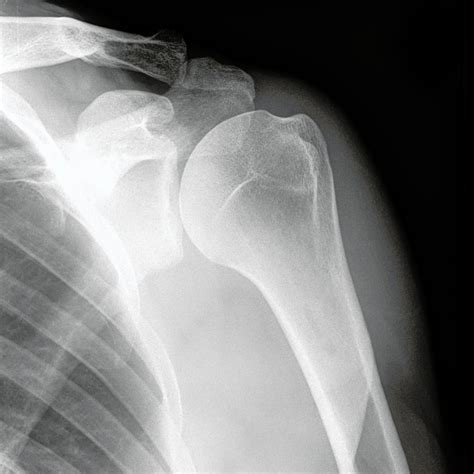

X Ray Shoulder Normal

When you experience persistent shoulder pain or restricted mobility, a medical professional will often order imaging to get a better look at what is happening beneath the surface. One of the first lines of investigation is almost always an X-ray shoulder normal view, which provides a foundational baseline for orthopedic health. Understanding what this diagnostic tool shows and why it is essential for clinical decision-making can help alleviate the anxiety often associated with medical imaging. While an X-ray is a standard procedure, it remains a powerful instrument for identifying fractures, dislocations, and degenerative changes that may be causing your discomfort.

An X-ray of the shoulder is a non-invasive imaging test that uses a small amount of radiation to capture internal pictures of the shoulder bones. This includes the humerus (upper arm bone), the scapula (shoulder blade), and the clavicle (collarbone). By analyzing these images, radiologists and doctors can determine if there are any anatomical abnormalities, structural issues, or signs of disease.

Typically, when a radiologist reports an X-ray shoulder normal result, they are confirming that the skeletal structures are well-aligned, the joint space is intact, and there are no signs of acute trauma or advanced chronic conditions. This is often the starting point for diagnosis; if the bones appear healthy, the physician can then narrow the focus to soft tissue injuries like rotator cuff tears or labral issues, which often require further investigation such as an MRI.

When you undergo this procedure, the imaging team typically captures multiple views to ensure a comprehensive assessment. These usually include an Anteroposterior (AP) view, an axillary view, and a lateral view (often called a "Y-view"). These angles allow the physician to look for specific markers of health:

• Bone Integrity: Ensuring there are no hairline fractures or stress reactions in the humerus or clavicle.

• Joint Space: Checking for smooth, consistent gaps between bones, which indicates healthy cartilage.

• Alignment: Verifying that the humeral head sits correctly within the glenoid fossa (the socket of the shoulder).

• Soft Tissue Shadows: Looking for calcification, which might suggest conditions like calcific tendinitis.